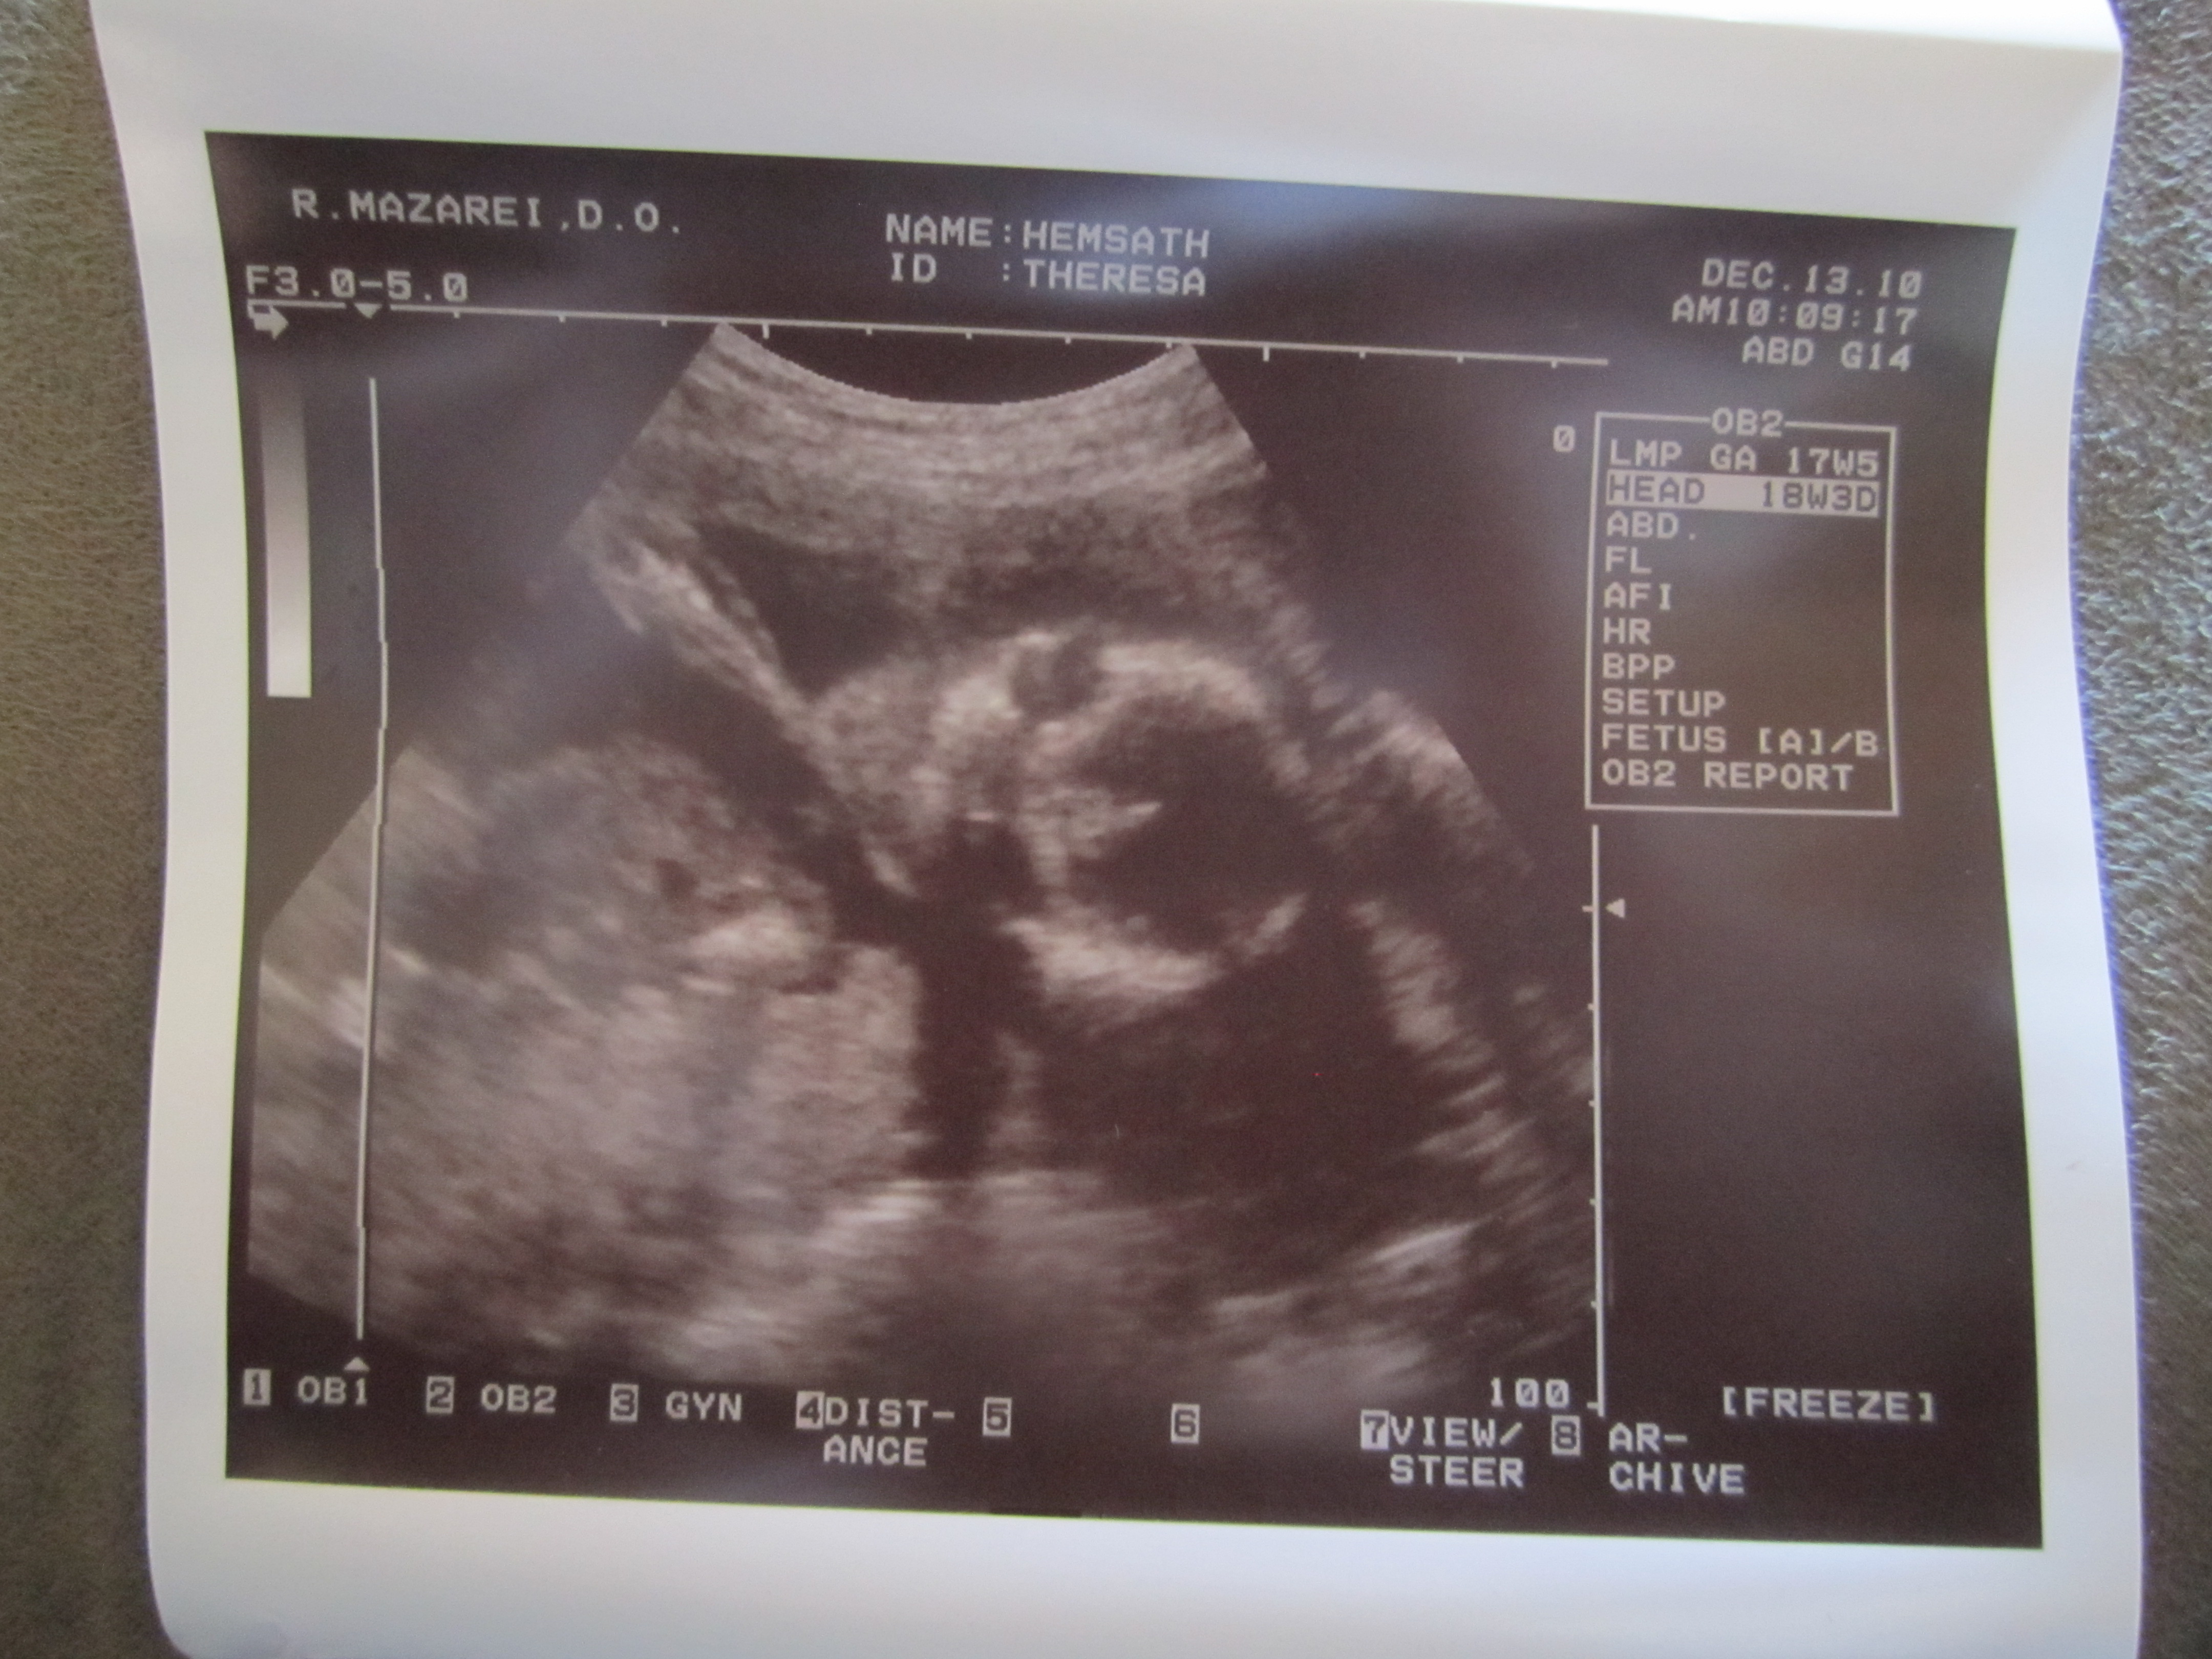

- Talking to Kanan about the baby. He kisses my belly. He tells me he loves his baby brother or sister. He wants him to be a girl and to name her Allison (Even though the ultrasound showed us it is a boy and we think we may name him Mathias or Mateo). He wants me to hold the baby and him or to have Papa (Owen’s name) hold the baby and I hold him. He wants to help feed the baby and hold the baby too. So darn cute! Oh yeah, and he loves watching videos from Baby Center that shows the development of the baby in the womb.

- All the medical scares that come with being pregnant in the 21st century. What ever happened to just being pregnant and having a baby? Now I’ve got to do blood tests and ultrasounds and if anything is slightly off, they scare me with all the what if’s, risks, and possibilities and then want me to do all these other medical procedures. I believe it’s a greedy conspiracy for money.